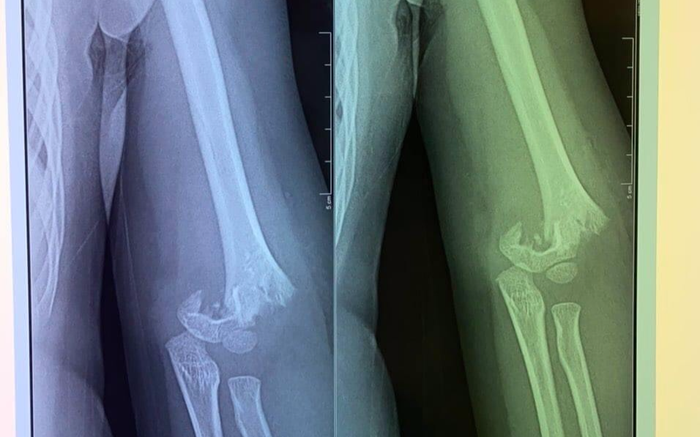

Tại bệnh viện, khi cô giáo thông báo cho mẹ cháu bé vào làm thủ tục để nhập viện, khi đó chị H. vô cùng bất ngờ khi biết con bị mổ cấp cứu, có nguy cơ bị liệt, đau đớn hơn khi xem phim chụp thấy hình ảnh xương ở khuỷu tay của con đã bị gãy lìa.

Hình ảnh xương cháu bé bị gãy rời khiến nhiều người xót xa.